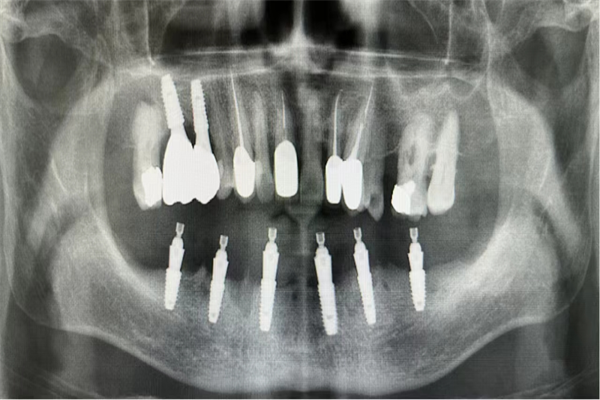

手術(shù)當(dāng)天,楊濤主任和王可醫(yī)生在麻醉科的協(xié)助下,整個拔牙及種植過程十分順利。術(shù)后X線片顯示,種植體的植入深度、角度,高度都非常精準(zhǔn)。

術(shù)后X線檢查,確認(rèn)種植體植入位置